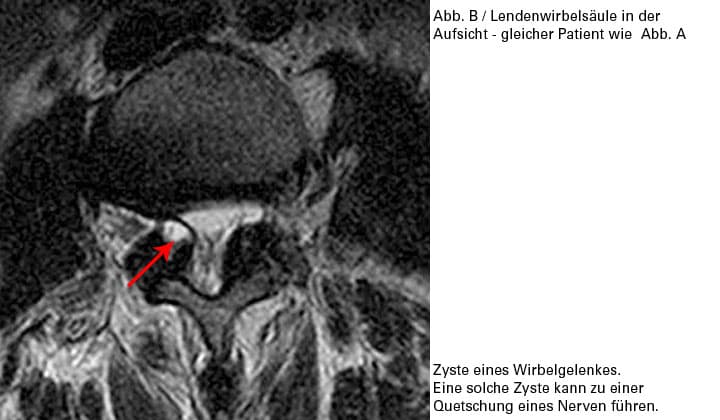

In extrem seltenen Fällen kann ein Gelenkerguss zu einer Schleimhaut-Cyste führen, die wie ein BSV eine Nervenwurzelquetschung verursachen kann.